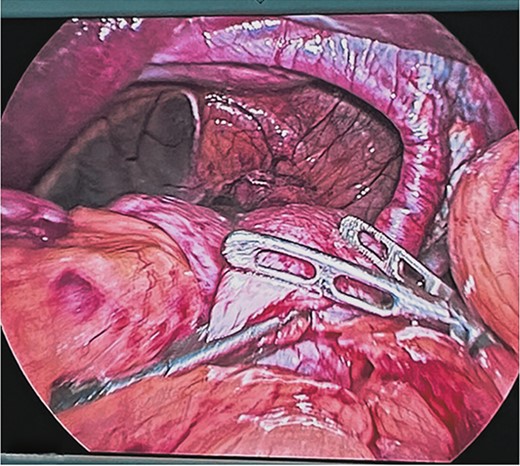

Surgical treatment was decided. Five ports were used: one supraumbilical 12 mm port for the telescope, one 5 mm subxiphoid port for the liver retractor, and three working ports placed in the left midclavicular line of 12 mm, the left axillary line of 5 mm, and the right midclavicular line of 5 mm. A type IV hiatal hernia was found with a 12 cm hernia defect (Fig. 3), a hernia sac measuring 20 cm × 15 cm × 7 cm, containing the entire stomach, dudodenum, pancreas, greater omentum, and transverse colon. The content was reduced to subsequently dissect and resect the hernia sac (Fig. 4).

Dissection and resection of hernial sac with traction and monopolar energy.